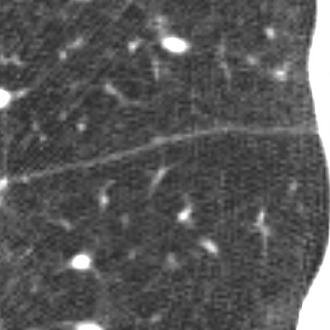

Pulmonary fissures are the most accurate feature for lobe segmentation but these are often incomplete and there can be accessory fissures in the lungs. We train a 3D u-net to rely on visible fissures and simultaneously learn that fissures are often incomplete.

The most promising features for lung lobe segmentation can be found at the lobar boundaries. We want our networks to learn two facts: 1. pulmonary fissures are at the lobar boundaries, but 2. there might be no fissures at the lobar boundaries (incomplete fissures). Therefore we introduce a weighted Dice loss in the following manner: We calculate an Euclidean distance transformation (EDT) from the lobar boundaries of the reference segmentation. Next, we invert the distance dist within a radius of 10 mm by setting the values to 10 - dist and set the remaining part of the lungs to a value of 1. This results in a weighting image with a value of 10 at the lobar boundaries descending to value 1 within 10 mm radius. We use the EDT because the reference segmentation might not be exact on the lobar boundaries and we do not want to miss information from visible fissures. Thus, we use the following loss function: